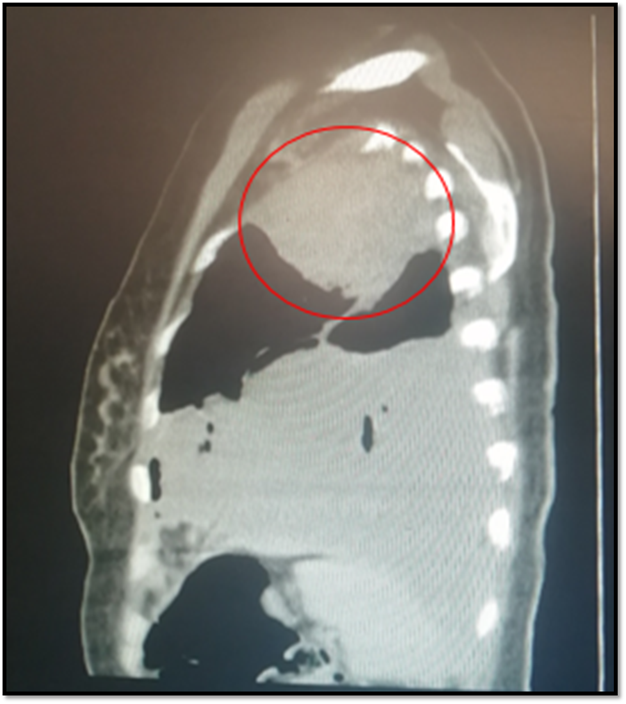

The next study to be requested will be the computerized axial tomography of the simple thorax, which will describe in a more specific way the size, location and extension of the lesion, as well as the presence of lesions suggestive of metastasis at lymphatic and bone level. Another alternative study is MRI of the chest, with similar sensitivity and specificity.

From the outset, a chest radiography is requested, where there is evidence of left pleural effusion that takes the base and third, where the opacity of approximately 5x5cm in the upper ipsilateral vertex draws attention. A sample of this pleural fluid (cytological, cytochemical and culture) is taken, this being negative. Simple chest tomography is performed where the following is observed:

@anaestrada12

Space-occupying lesion with mass effect at left pulmonary vertex level of approximately 5x 7,2cm. Accompanied by septate ipsilateral effusion.

Suggestive images of bone metastasis at t5, t4 and sternum levels are also observed.